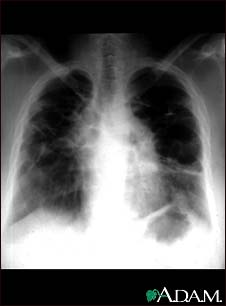

Sarcoid, stage IV - chest X-ray

This film shows advanced sarcoid, scarring of the lungs (the light streaking), and cavity formation (the dark areas in the upper right side of the picture).